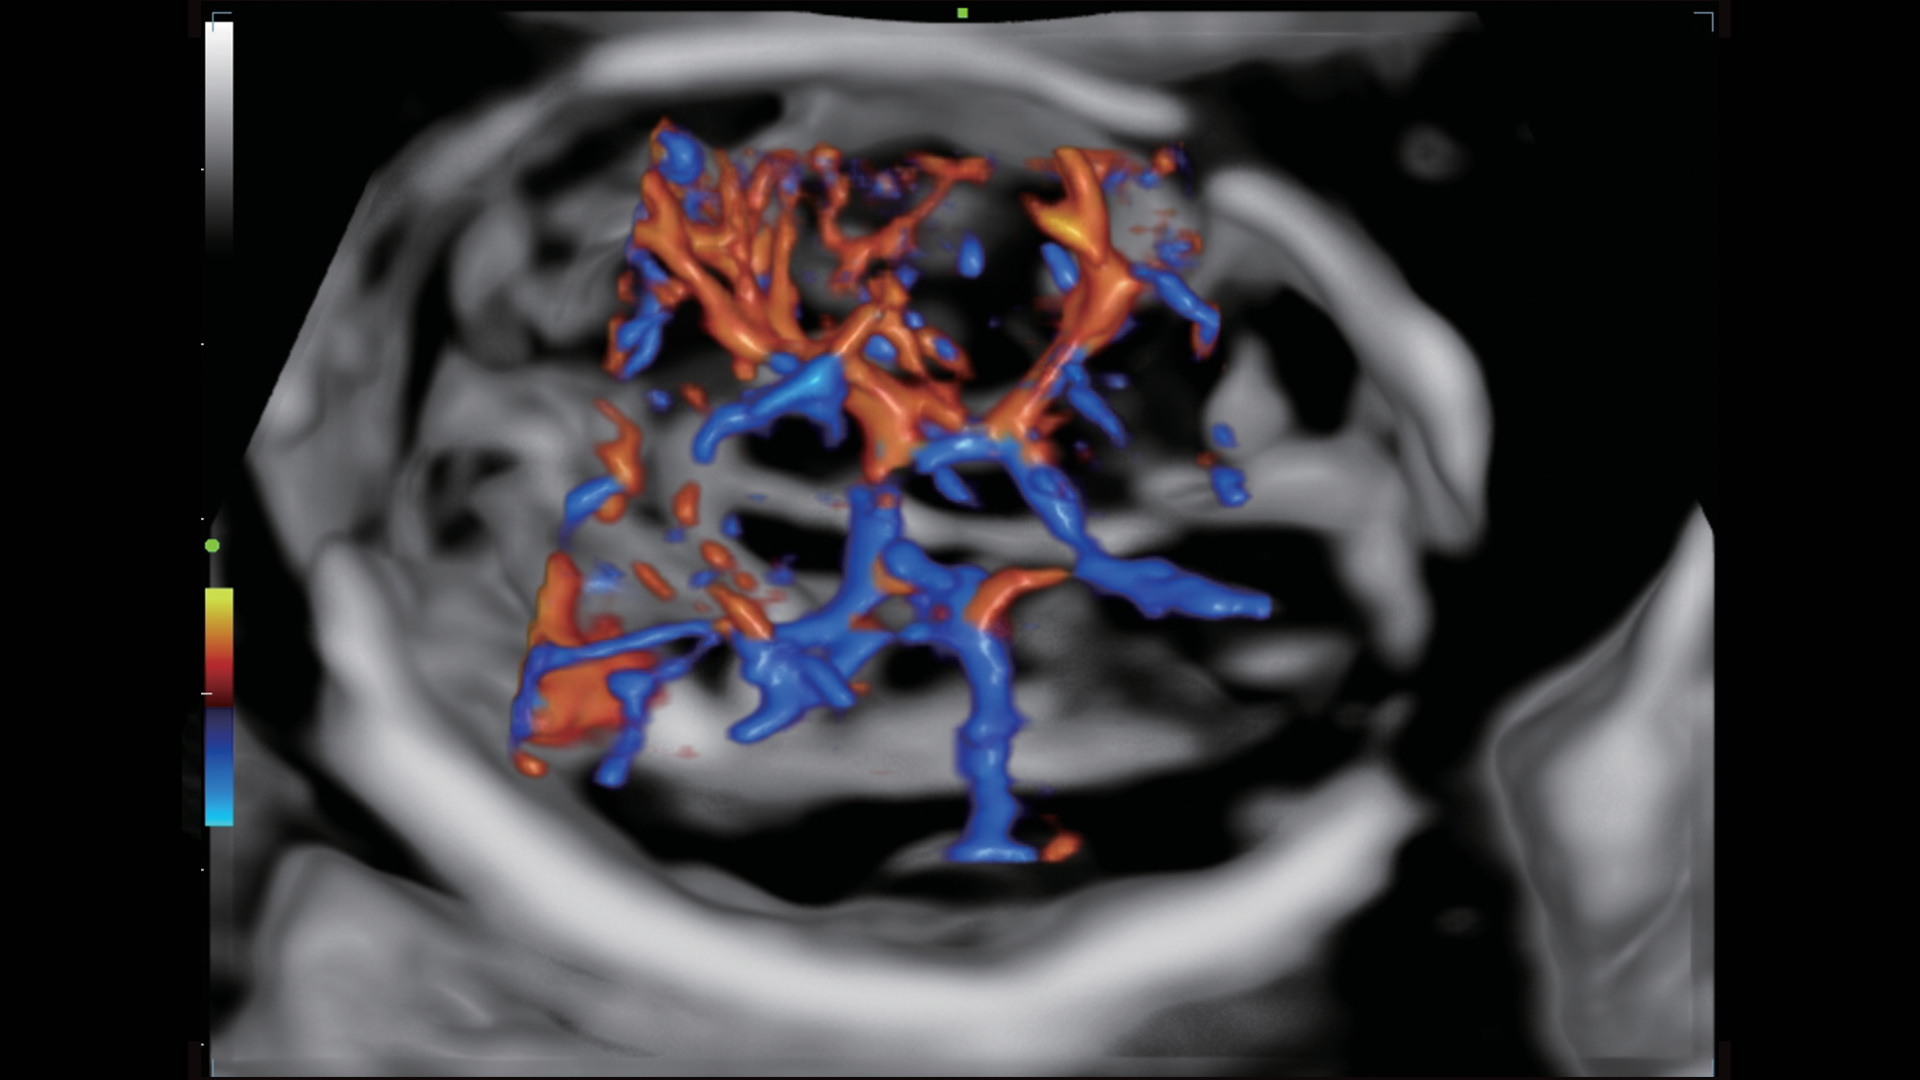

UMA (Ultra-Micro Angiography)

The innovative technology breaks the bottlenecks of traditional Doppler imaging. With ultra-high spatial resolution and flow sensitivity, it allows detecting super-subtle and super-slow flow perfusions, thereby extending the clinical application of qualitative and quantitative ultrasound evaluation in fetal brain, kidney, placenta, endometrium, ovary, etc.

3D UMA - fetus intracranial flow

3D UMA - perifollicular blood flow